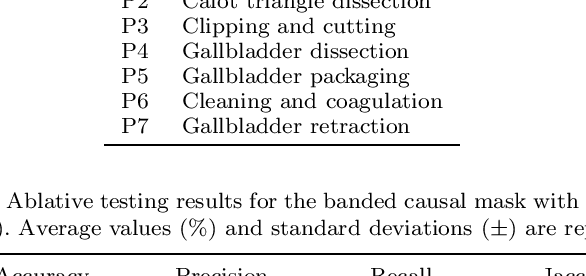

ARST: Auto-Regressive Surgical Transformer for Phase Recognition from Laparoscopic Videos

Sep 02, 2022

Abstract:Phase recognition plays an essential role for surgical workflow analysis in computer assisted intervention. Transformer, originally proposed for sequential data modeling in natural language processing, has been successfully applied to surgical phase recognition. Existing works based on transformer mainly focus on modeling attention dependency, without introducing auto-regression. In this work, an Auto-Regressive Surgical Transformer, referred as ARST, is first proposed for on-line surgical phase recognition from laparoscopic videos, modeling the inter-phase correlation implicitly by conditional probability distribution. To reduce inference bias and to enhance phase consistency, we further develop a consistency constraint inference strategy based on auto-regression. We conduct comprehensive validations on a well-known public dataset Cholec80. Experimental results show that our method outperforms the state-of-the-art methods both quantitatively and qualitatively, and achieves an inference rate of 66 frames per second (fps).